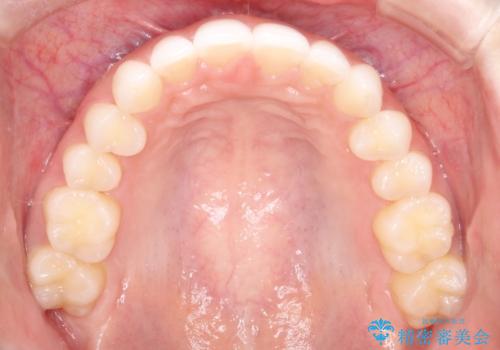

出っ歯の矯正治療 歯を抜かずにインビザラインで

- インビザラインで出っ歯を治したいとの希望がありました。

上顎の歯を全体的に後方に移動させて前歯を引っ込める計画としました。

インビザラインで目立たずに、痛みも少なく矯正治療を終えることができ満足していただけました。